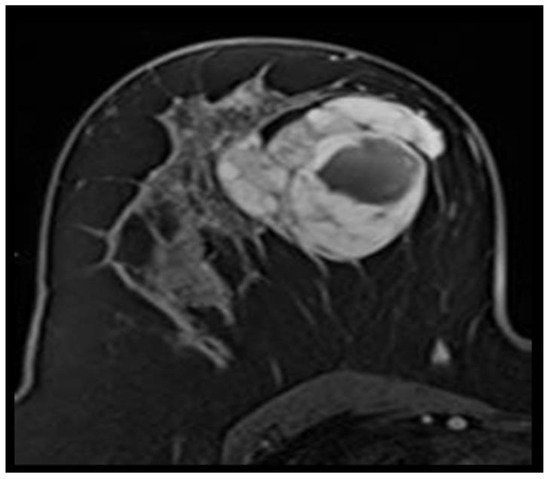

Fibromatosis

Angiolipoma